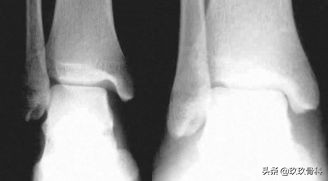

辅助检查

- X线 踝关节正侧位(必要时应加照踝穴位)

- B超

- MRI

应力位片